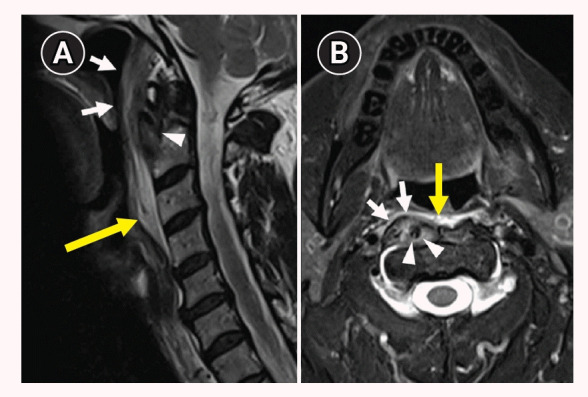

Calcific tendinitis of the longus colli muscle.

领长肌钙化性腱鞘炎